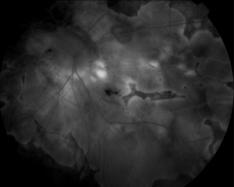

IM000037.JPG